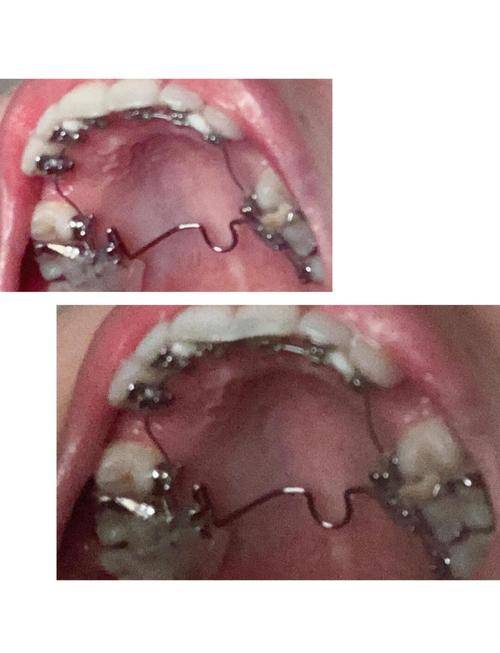

- 极致美观: 这是舌侧矫正最大的吸引力,托槽和弓丝完全隐藏在牙齿内侧,从外面完全看不到,对于32岁这个职场社交活跃的年龄,美观需求非常高,舌侧矫正能让你在矫正过程中完全不用担心“钢牙”形象,工作、社交、拍照都非常自信。

- 个性化定制: 舌侧托槽通常是间接粘接的,需要取模后由技师在模型上精确粘好托槽,然后由医生转移到你口内,这种定制化方式能更精确地控制牙齿移动,理论上可以达到非常精细的矫正效果。

- 粘接难度大: 舌侧托槽粘接在牙齿内侧,视野受限,操作空间小,对医生的技术和经验要求极高,选择一位经验丰富、专门从事舌侧矫正的医生是成功的关键,操作不当会导致托槽脱落频繁、效率低下、甚至损伤牙齿。

- 舌头刺激: 舌头不断接触内侧的托槽和弓丝,初期会有明显的异物感、刺痛感、溃疡,影响说话、吞咽和进食,需要一段时间的适应(通常1-2周)。

- 口腔清洁难度大: 舌侧矫正的清洁比传统矫正和隐形牙套都困难得多,托槽和弓丝在牙齿内侧,牙刷很难有效清洁,容易堆积食物残渣和菌斑,大大增加蛀牙和牙龈炎的风险,需要学习并严格执行非常细致的清洁方法(如使用正畸专用小头牙刷、牙缝刷、冲牙器、牙线牵引器等),并定期进行专业洗牙。

- 对牙齿形态有一定要求: 舌侧托槽体积相对较大,对于牙齿特别小或者形态不规则的牙齿,可能难以粘接或效果不佳,医生需要在面诊时评估。